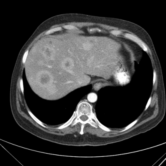

The category discovery clusters employing our LDPO method are found to be more visually coherent and cluster-wise balanced in comparison to the results in [44] where clusters are formed only from text information ( radiology reports). Fig. 4 Left shows the image numbers for each cluster from the AlexNet-FC7-Topic setting. The numbers are uniformly distributed with a mean of 778 and standard deviation of 52. Fig. 4 Right illustrates the relation of clustering results derived from image cues or text reports [44]. Note that there is no instance-balance-per-cluster constraints in the LDPO clustering. The clusters in [44] are highly uneven: 3 clusters inhabit the majority of images. Fig. 5 shows sample images and top-10 associated key words from 4 randomly selected clusters (more results in the supplementary material). The LDPO clusters are found to be semantically or clinically related to the corresponding key words, containing the information of (likely appeared) anatomies, pathologies (e.g., adenopathy, mass), their attributes (e.g., bulky, frontal) and imaging protocols or properties.

Next, from the best performed LDPO models in Table 2, AlexNet-FC7-Topic has Top-1 classification accuracy of 0.8109 and Top-5 accuracy 0.9412 with 270 formed image categories; AlexNet-FC7-ImageNet achieves accuracies of 0.8099 and 0.9547, respectively, from 275 discovered classes. In contrast, [44] reports Top-1 accuracies of 0.6072, 0.6582 and Top-5 as 0.9294, 0.9460 on 80 text only computed classes using AlexNet [27] or VGGNet-19 [47], respectively. Markedly better accuracies (especially on Top-1) on classifying higher numbers of classes (being generally more difficult) highlight advantageous quality of the LDPO discovered image clusters or labels. This means that the LDPO results have rendered significantly better performance on automatic image labeling than the most related previous work [44], under the same radiology database. After the subjective evaluation by two board-certified radiologists, AlexNet-FC7-Topic of 270 categories and AlexNet-FC7-ImageNet of 275 classes are preferred, out of total six model-encoding setups. Interestingly, both CNN models have no deep feature encoding built-in and preserve the gloss image layouts (capturing somewhat global visual scenes without unordered FV or VLAD encoding schemes [9, 8, 21].).

The final trained CNN classification models allow to compute the pairwise category similarities or affinity scores using the CNN classification confusion values between any pair of classes (Sec. 3.5). Affinity Propagation algorithm is called recursively to form a hierarchical category tree. The resulted category tree has (270, 64, 15, 4, 1) different class labels from bottom (leaf) to top (root). The random color coded category tree is shown in Fig. 6. The high majority of images in the clusters of this branch are verified as CT Chest scans by radiologists. Enabling to construct a semantic and meaningful hierarchy of classes offers another indicator to validate the proposed LDPO category discovery method and results. Refer to the supplementary material for more results. We will make our trained CNN models, computed deep image features and labels publicly available upon publication.